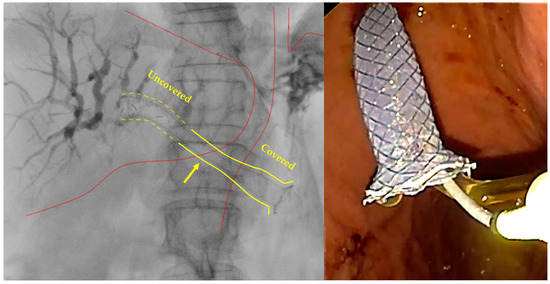

- Stent positioning